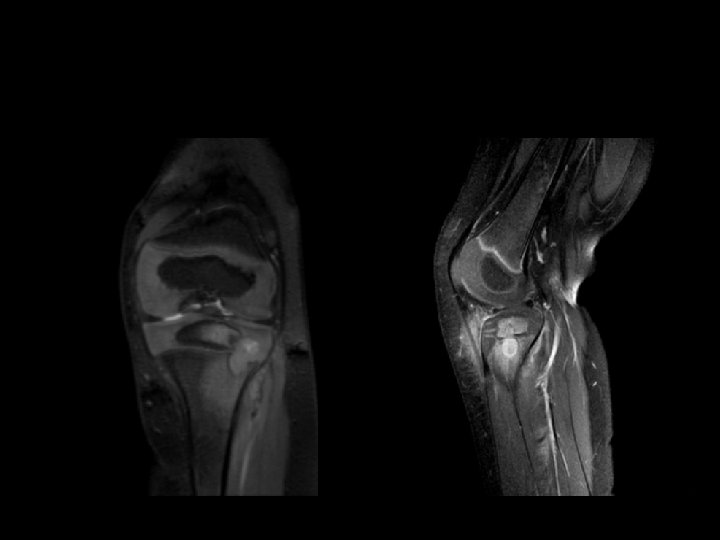

IRM � • Apprécier la stabilité du fragment • Cartilage articulaire • Intérêt des séquences « cartilage »

Critères pronostiques à l’IRM • Taille de la lésion +++++ • Liseré hyper intense ? ? ? • Kystes périlésionnels ?

osteochondritis dissecans L true-FISP WARM UP ACUTE INJURIES CHRONIC INJURIES COOL DOWN